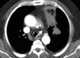

Aorticopulmonary paraganglioma